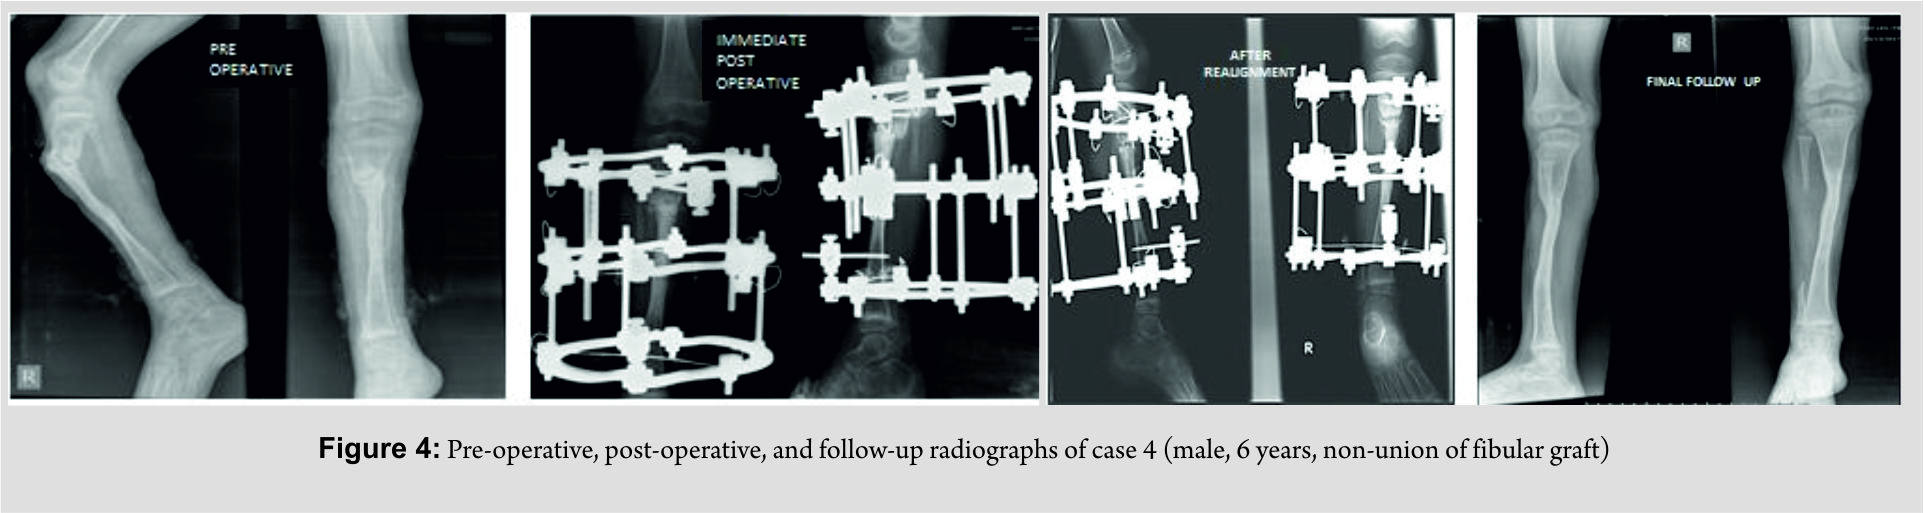

We had four children (3 males and 1 female, age 4–15 years) with hypertrophic nonunion of the tibia. Three of them were post-traumatic. The fourth patient had tibial bone defect following acute osteomyelitis. He underwent tibialisation of the fibula elsewhere. The distal junction united uneventfully, but the proximal junction went in for hypertrophic nonunion. The demographic and clinical characteristics of our patient cohort are summarized in Table 1 (Fig. 1, 2, 3, 4).

All patients had a follow-up of 2 years from the removal of external fixator. All four non-unions united uneventfully. In the two patients were deformity correction was completed in two stages, compression commenced after 3 days after second surgery. (No manipulation was done during the week in between two stages as it would inadvertently stretch the soft tissue.) Another patient (where all deformities were acutely corrected) developed minimal swelling of the limb and blebs on the 2nd day. It responded to limb elevation and delay of rehabilitation. Compression was started after a latent period of 7 days. In the fourth patient, the latent phase lasted only for 3 days. After completion of “dynamic” phase, patients were sent home with advice to follow-up every 6 weeks. Three of the nonunions were united at the second follow-up (12 weeks) and the fourth at third follow-up (18 weeks). Thus, the total duration of external fixator was 14 weeks in one patient, 15 weeks in two patients, and 21 weeks in the fourth patient. The fixators were removed after satisfactory stress test after loosening all connecting rods. Patellar tendon bearing cast was given for all cases for 6 weeks with the advice of full weight-bearing. Apart from limb swelling and blebs in one case, another patient had pin tract infection that was detected at first follow-up that needed a week of dressings and oral antibiotics. The infection settled uneventfully without any need of wire exchange. Two patients each had minimal residual deformity and shortening <1 cm, well within acceptable limits with potential to remodel. The intraoperative, post-operative, and follow-up characteristics of our patient cohort are summarized in Table 2 (Fig. 1, 2, 3, 4).

The fixators were removed after satisfactory stress test after loosening all connecting rods. Patellar tendon bearing cast was given for all cases for 6 weeks with the advice of full weight-bearing. Apart from limb swelling and blebs in one case, another patient had pin tract infection that was detected at first follow-up that needed a week of dressings and oral antibiotics. The infection settled uneventfully without any need of wire exchange. Two patients each had minimal residual deformity and shortening <1 cm, well within acceptable limits with potential to remodel. The intraoperative, post-operative, and follow-up characteristics of our patient cohort are summarized in Table 2 (Fig. 1, 2, 3, 4).